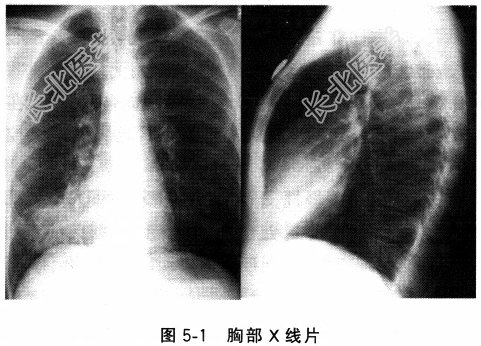

- 多项选择题3.患者血常规白细胞计数15.2×109/L,中性粒细胞0.88, 血气分析提示PaO258mmHg,PaCO241mmHg, pH7.38,肝功能、肾功能、血糖、电解质正常, 心电图为窦性心动过速,胸部X线片如图5-1, 根据结果,患者的补充诊断有哪些

A、右中叶肺不张

B、右中叶肺炎

C、Ⅰ型呼吸衰竭